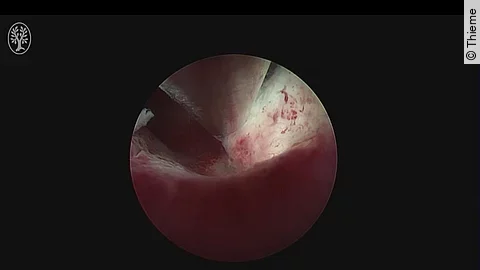

ThiemeOperative Hysteroskopie mit SeptumresektionFür Sie operierte Prof. Dr. Bernhard Krämer aus dem Department für Frauengesundheit Tübingen. Es moderierte: Prof. Dr. Bernhard Krämer.

ThiemeHysteroskopische SeptumdissektionFür Sie operierten und moderierten PD Dr. Bernhard Krämer und OA Dr. Felix Neis aus dem Department für Frauengesundheit Tübingen.